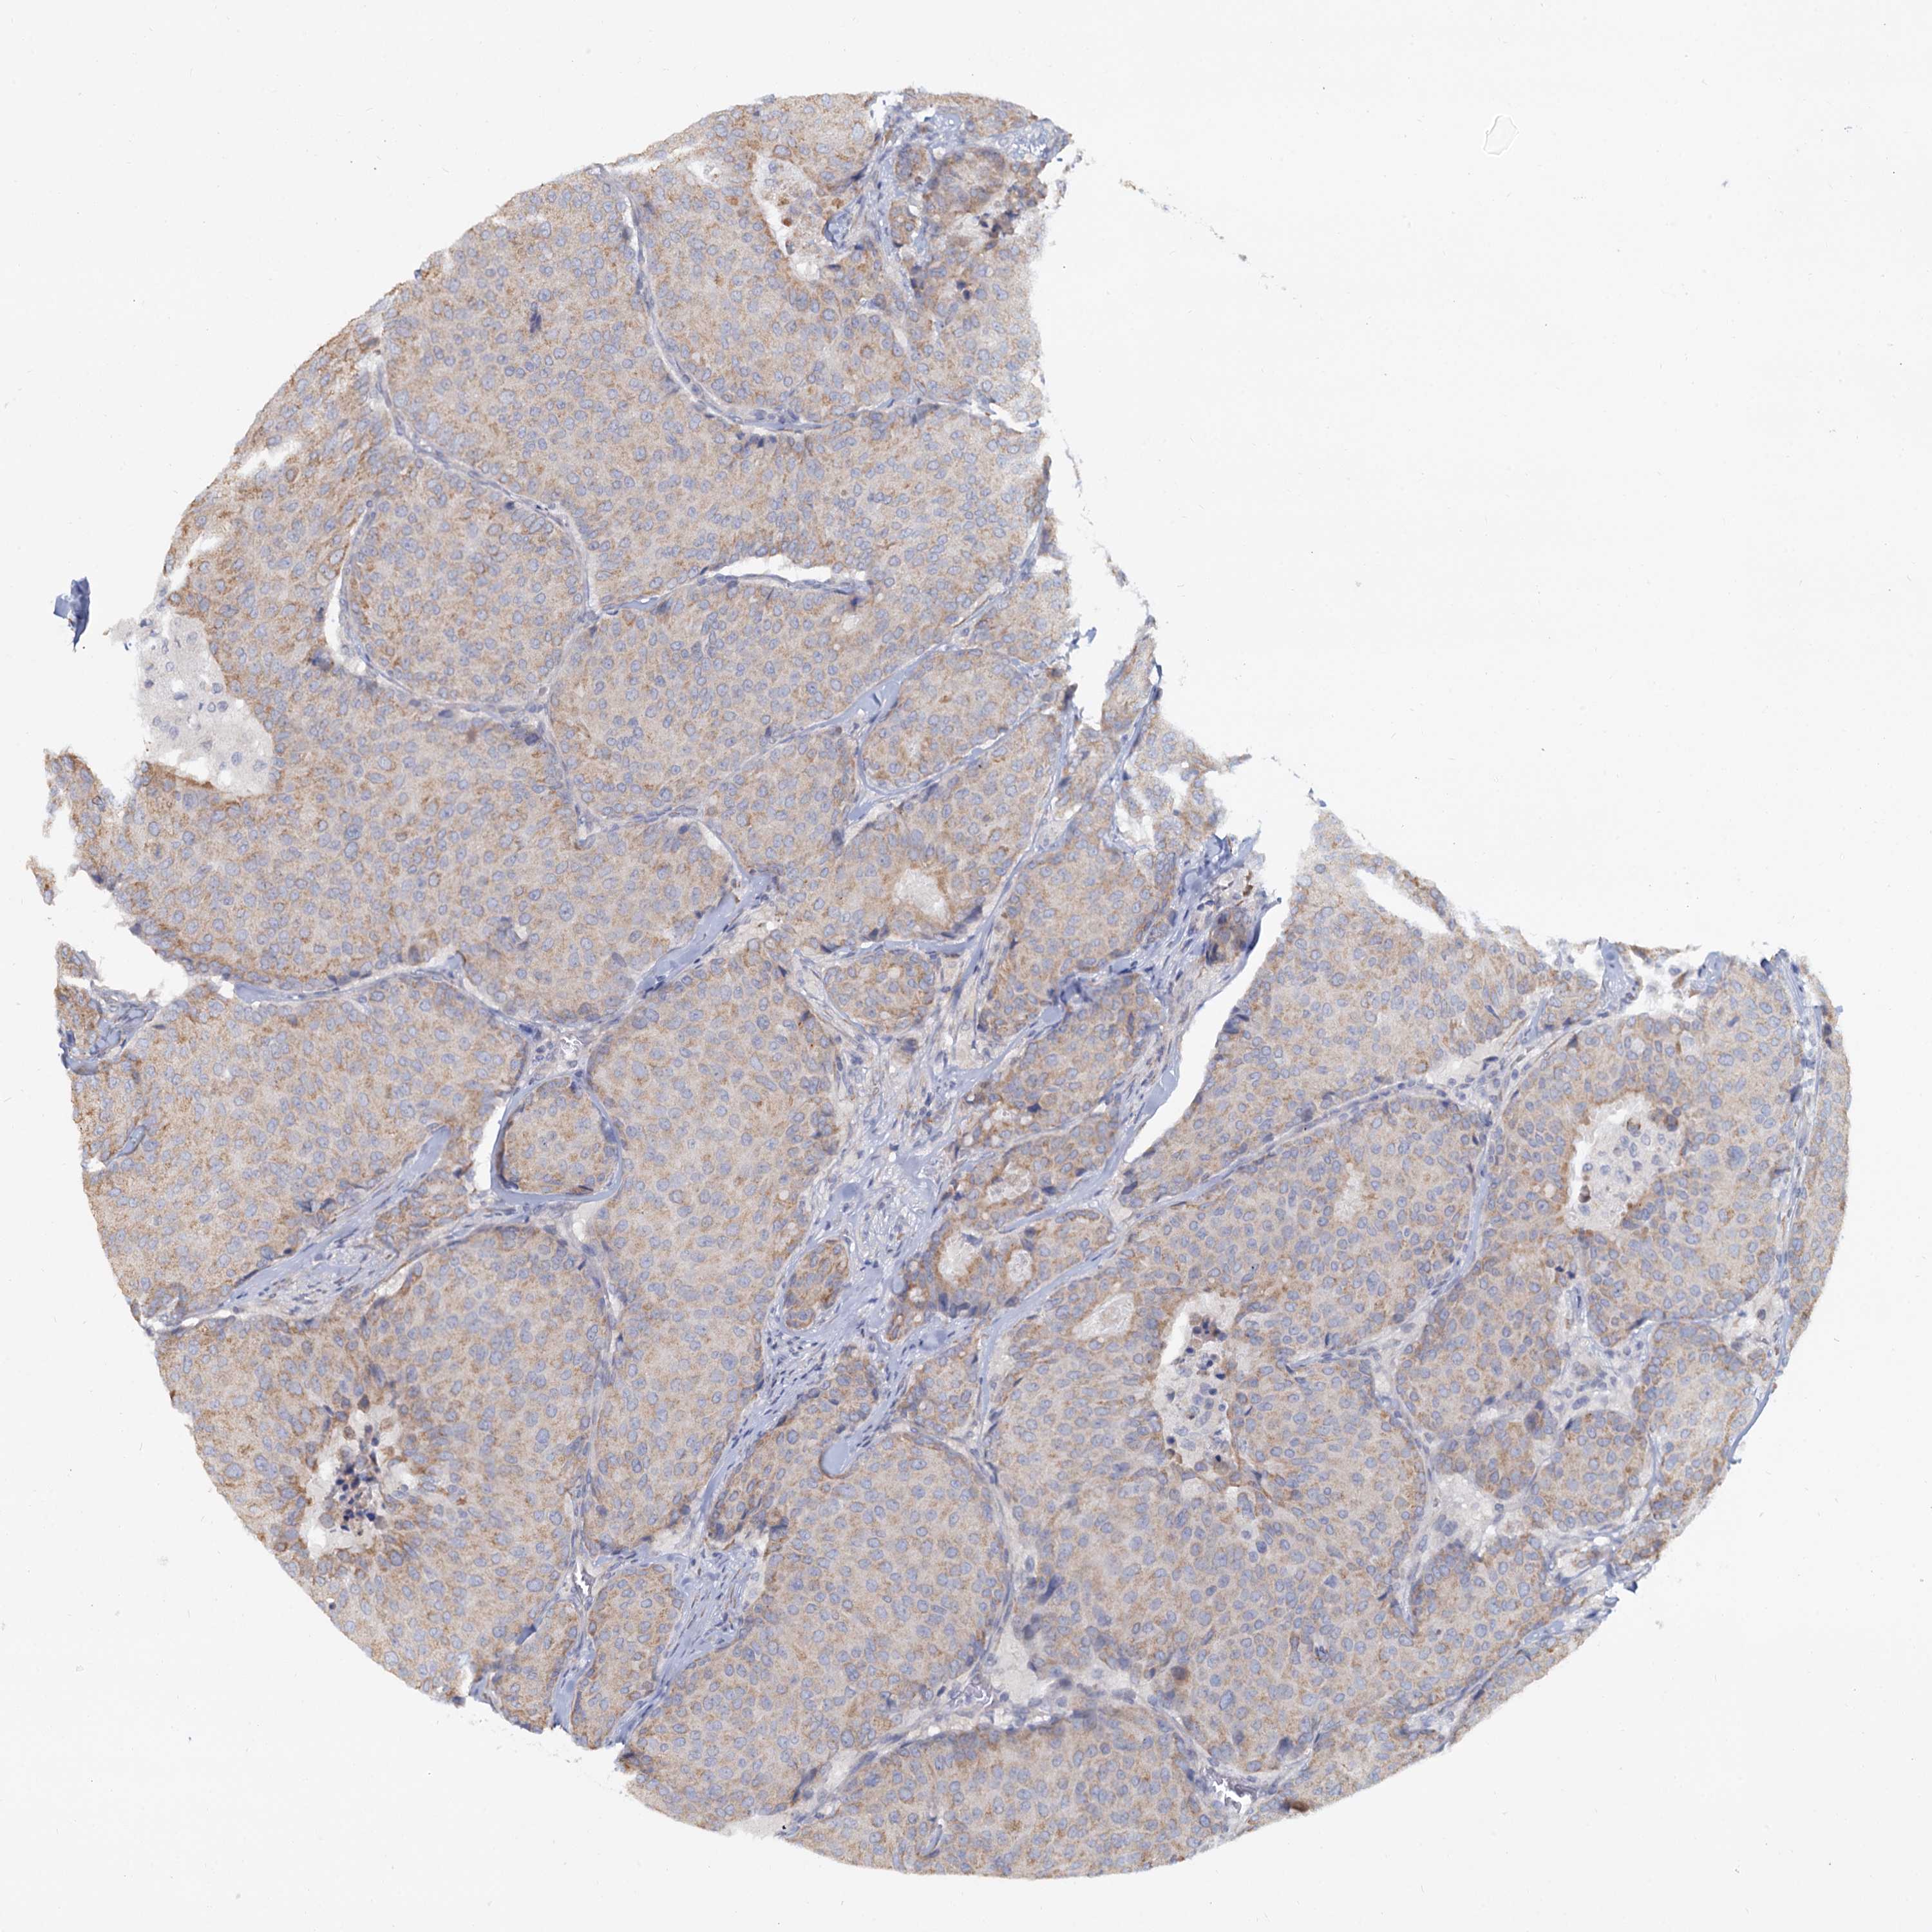

CANCER BREAST CANCER Show tissue menu

BRCA TCGA BRCA VALIDATION PROTEIN EXPRESSION

Breast cancer

Human cancer